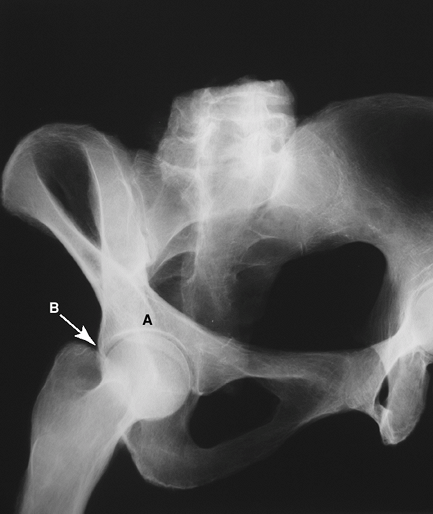

Figure 2-6 The anterior oblique or obturator oblique Judet view of the pelvis. A, anterior column of pelvis; B, posterior wall of acetabulum.

obtained by rotating the patient 45 degrees from the supine position

with the beam directed anteroposteriorly. They allow for visualization

of the columns and walls of the acetabulum and are used in evaluation

and classification of acetabular fractures as well as in the evaluation

of bone loss and osteolysis in patients with a failed acetabular

component. The two views are as follows: